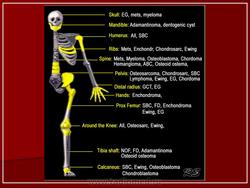

Дифференциальная диагностика изображения